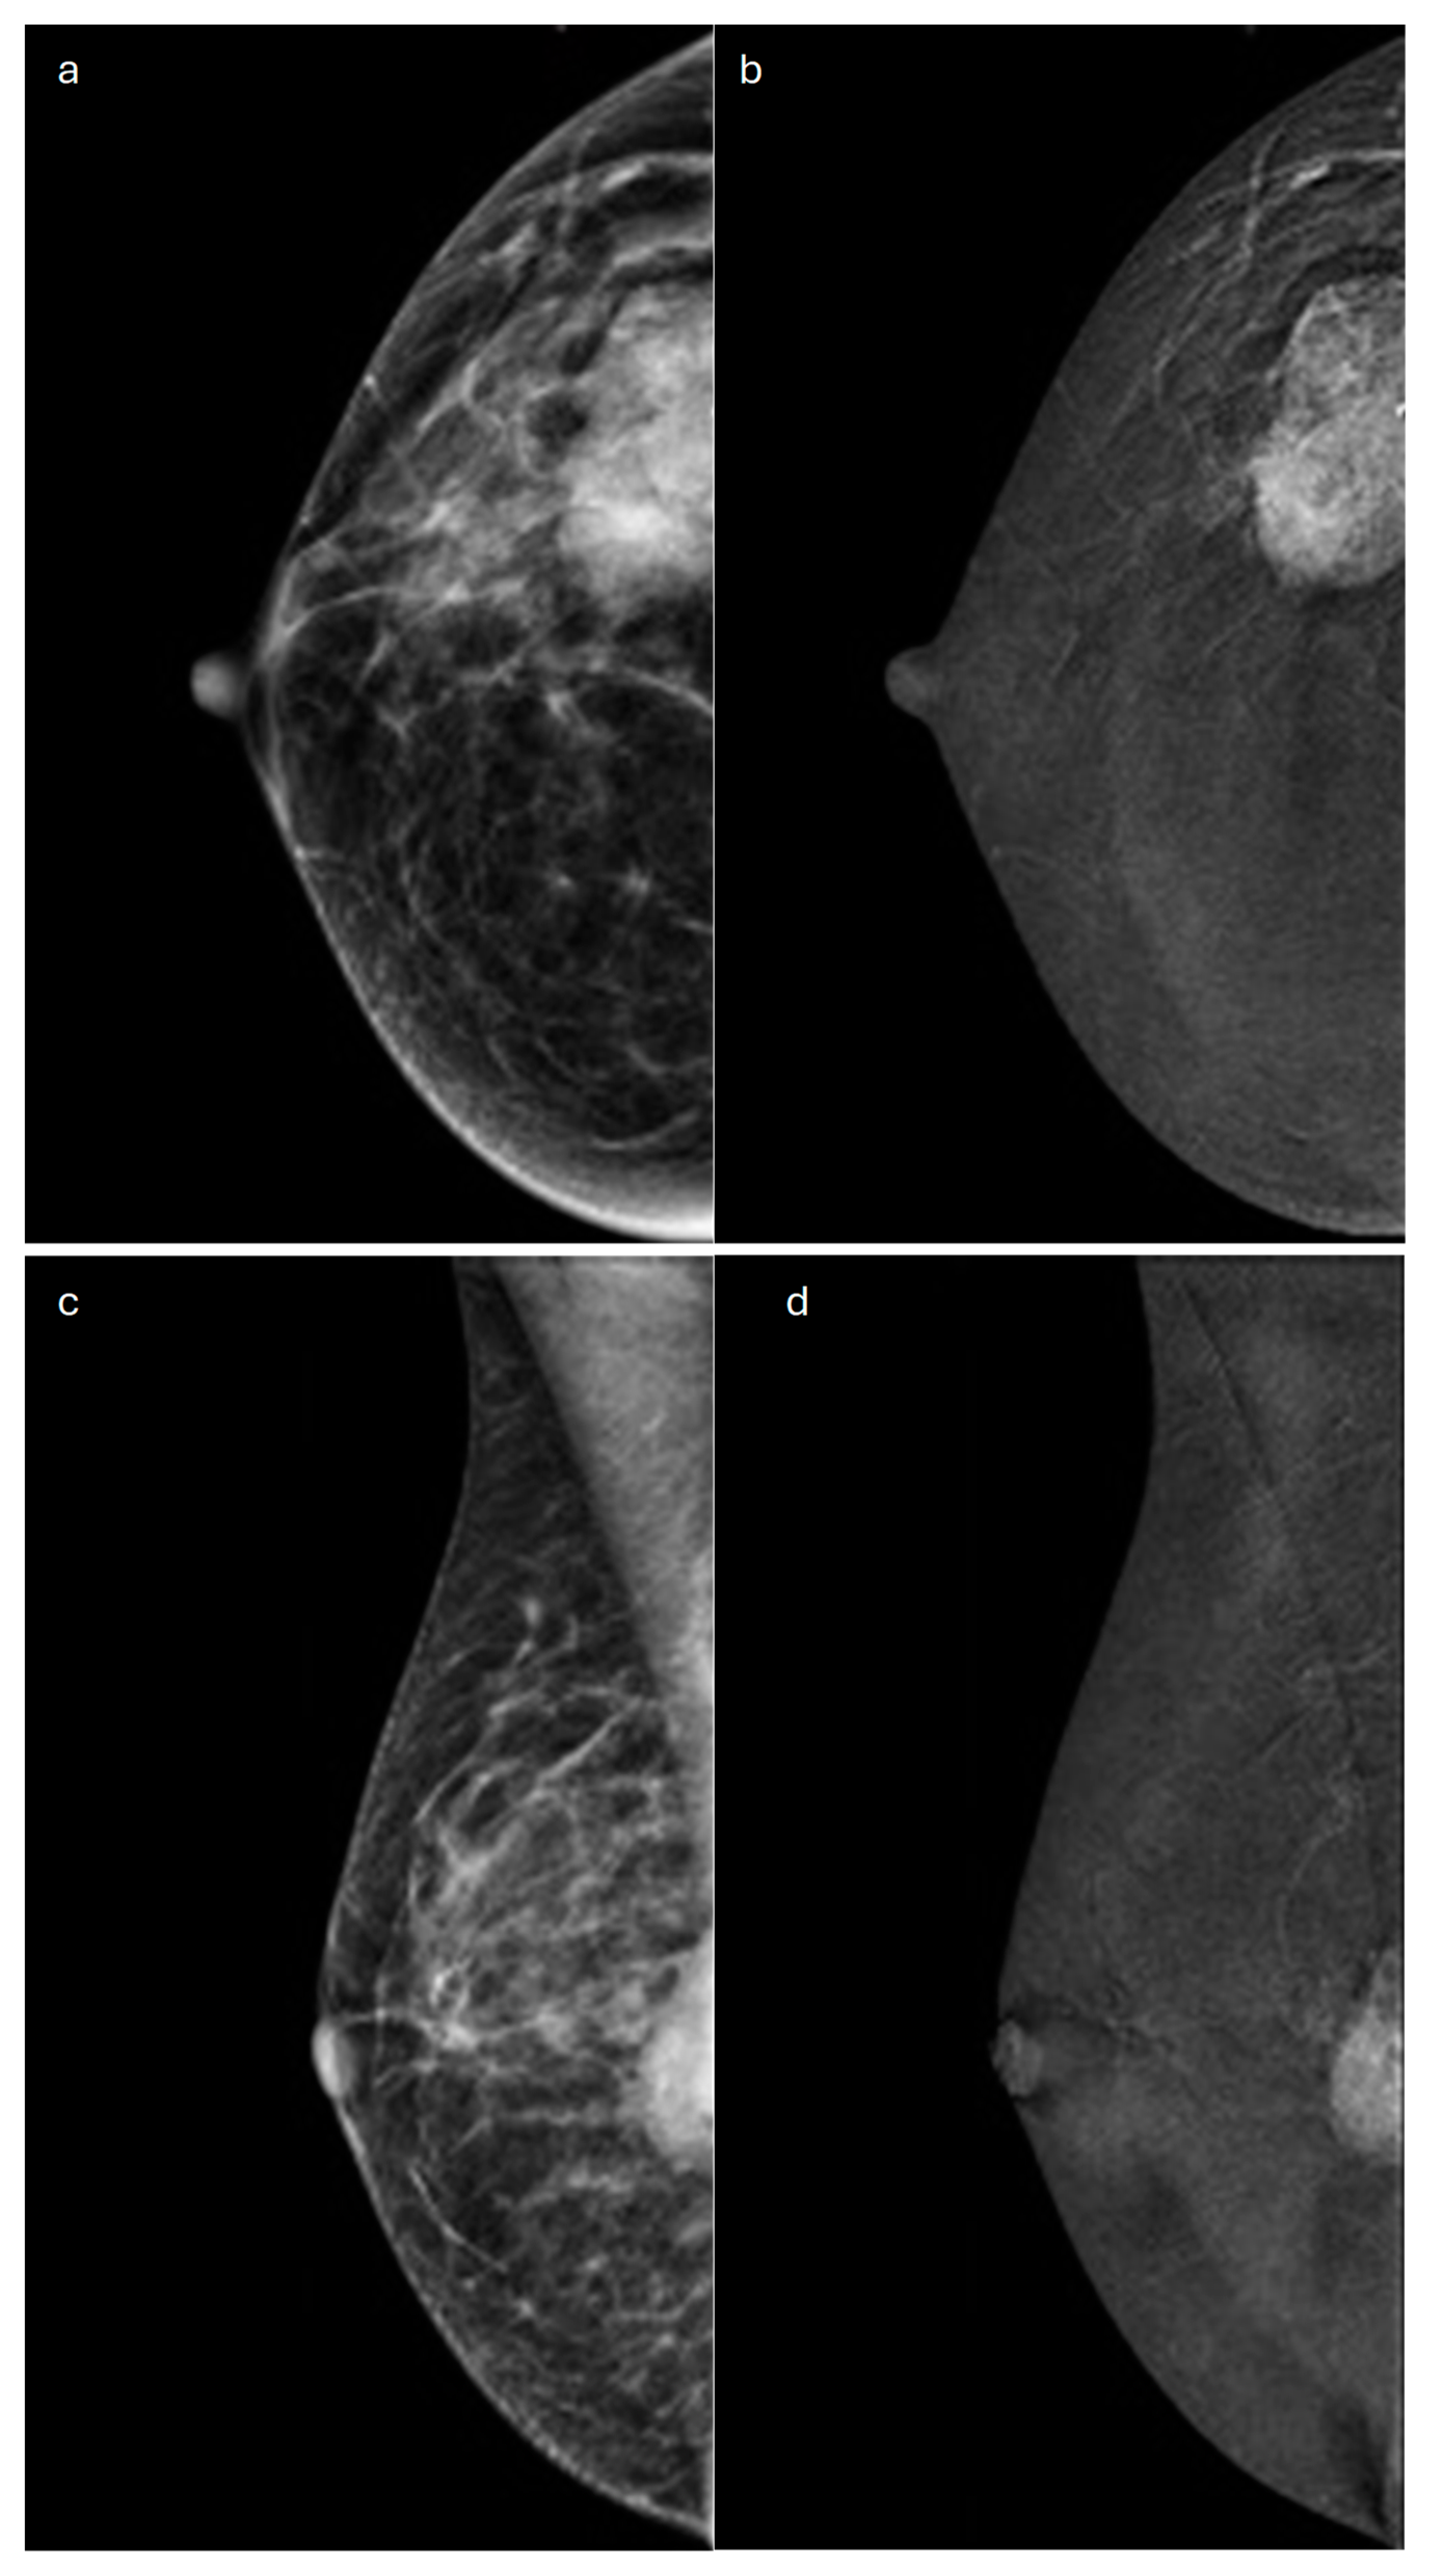

4. Mucinous

- Pintican, R.; Duma, M.; Chiorean, A.; Fetica, B.; Badan, M.; Bura, V.; Szep, M.; Feier, D.; Dudea, S. Mucinous versus Medullary Breast Carcinoma: Mammography, Ultrasound, and MRI Findings. Clin. Radiol. 2020, 75, 483–496. [Google Scholar] [CrossRef]

- Lam, W.W.M.; Chu, W.C.W.; Tse, G.M.; Ma, T.K. Sonographic Appearance of Mucinous Carcinoma of the Breast. AJR Am. J. Roentgenol. 2004, 182, 1069–1074. [Google Scholar] [CrossRef] [PubMed]

- Chaudhry, A.R.; El Khoury, M.; Gotra, A.; Eslami, Z.; Omeroglu, A.; Omeroglu-Altinel, G.; Chaudhry, S.H.; Mesurolle, B. Imaging Features of Pure and Mixed Forms of Mucinous Breast Carcinoma with Histopathological Correlation. Br. J. Radiol. 2019, 92, 20180810. [Google Scholar] [CrossRef]

- Memis, A.; Ozdemir, N.; Parildar, M.; Ustun, E.E.; Erhan, Y. Mucinous (Colloid) Breast Cancer: Mammographic and US Features with Histologic Correlation. Eur. J. Radiol. 2000, 35, 39–43. [Google Scholar] [CrossRef] [PubMed]

- Han, H.-J.; Kim, S.-H.; Cha, E.-S.; Kim, H.-S.; Kang, B.-J.; Choi, J.-J.; Lee, J.-H.; Lee, A.-W. Imaging Features of Mucinous Breast Carcinoma. Investig. Magn. Reson. Imaging 2010, 14, 21–30. [Google Scholar] [CrossRef]

- Bitencourt, A.G.V.; Graziano, L.; Osório, C.A.B.T.; Guatelli, C.S.; Souza, J.A.; Mendonça, M.H.S.; Marques, E.F. MRI Features of Mucinous Cancer of the Breast: Correlation with Pathologic Findings and Other Imaging Methods. AJR Am. J. Roentgenol. 2016, 206, 238–246. [Google Scholar] [CrossRef] [PubMed]

- Monzawa, S.; Yokokawa, M.; Sakuma, T.; Takao, S.; Hirokaga, K.; Hanioka, K.; Adachi, S. Mucinous Carcinoma of the Breast: MRI Features of Pure and Mixed Forms with Histopathologic Correlation. AJR Am. J. Roentgenol. 2009, 192, W125–W131. [Google Scholar] [CrossRef]